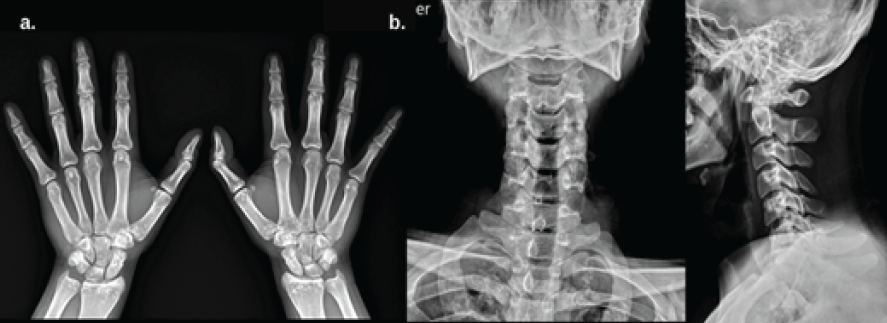

The ankle was immobilized in a neutral dorsiflexion position using a backslab, and the patient was admitted for further evaluation and surgical planning. During hospitalization, an extensive evaluation showed no associated conditions, skin lesions, or signs of endocrine dysfunction. Laboratory tests, including electrolytes, hematology, and urinalysis, were all within normal ranges. Thyroid and parathyroid hormones were normal. Vitamin D was decreased to 17 ng/mL. X-rays of other limbs showed similar well-defined sclerotic lesions in the distal radius and carpal bones (Fig. 2). CT scan of the ankle showed well-defined hyperintense foci in the cancellous bone of the distal tibia, consistent with OPK (Fig. 3).

Figure 2: (a) Anteroposterior (AP) X-ray of both hands showing well-defined sclerotic lesions in the distal radius and carpal bones, with no cortical involvement or periosteal reaction. (b) AP and lateral cervical spine X-rays showing symmetrically distributed sclerotic foci in vertebral bodies, without disc involvement or structural collapse.